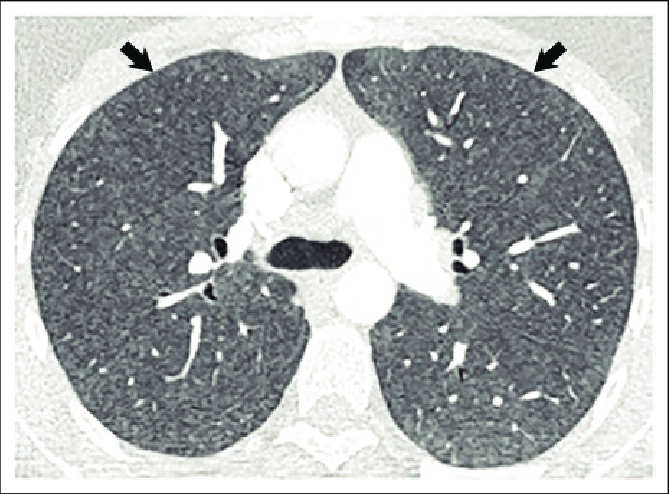

HRCT findings HP

patchy or diffuse lucency

mosaic attenuation

quickly normalises after antigen withdrawal